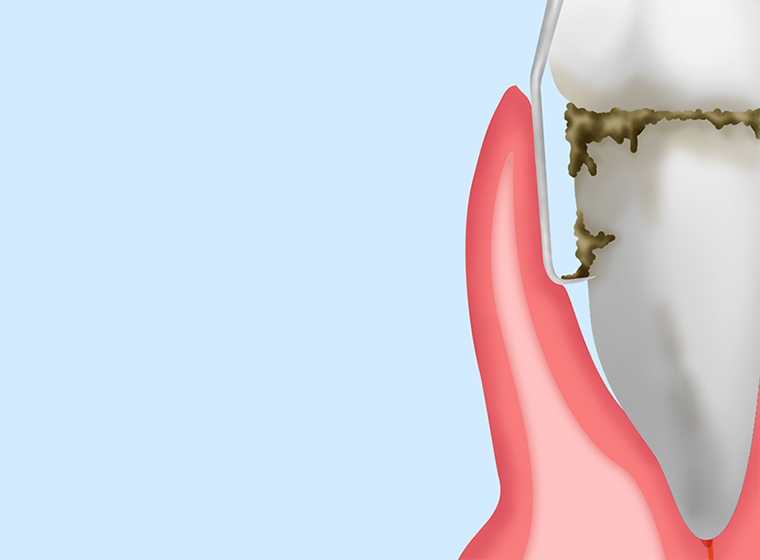

スケーリング

|

ブラッシングだけでは落とせない歯石を、スケーラーという器具を使って除去します。初期段階の歯周病への治療法です。 |

ルートプレーニング

|

スケーリングでは落としきれない歯周ポケットの奥に付着するプラーク(歯垢)や歯石を「キュレット」という器具で除去します。仕上げに歯面を滑らかにして汚れの再付着を防ぎます。 |